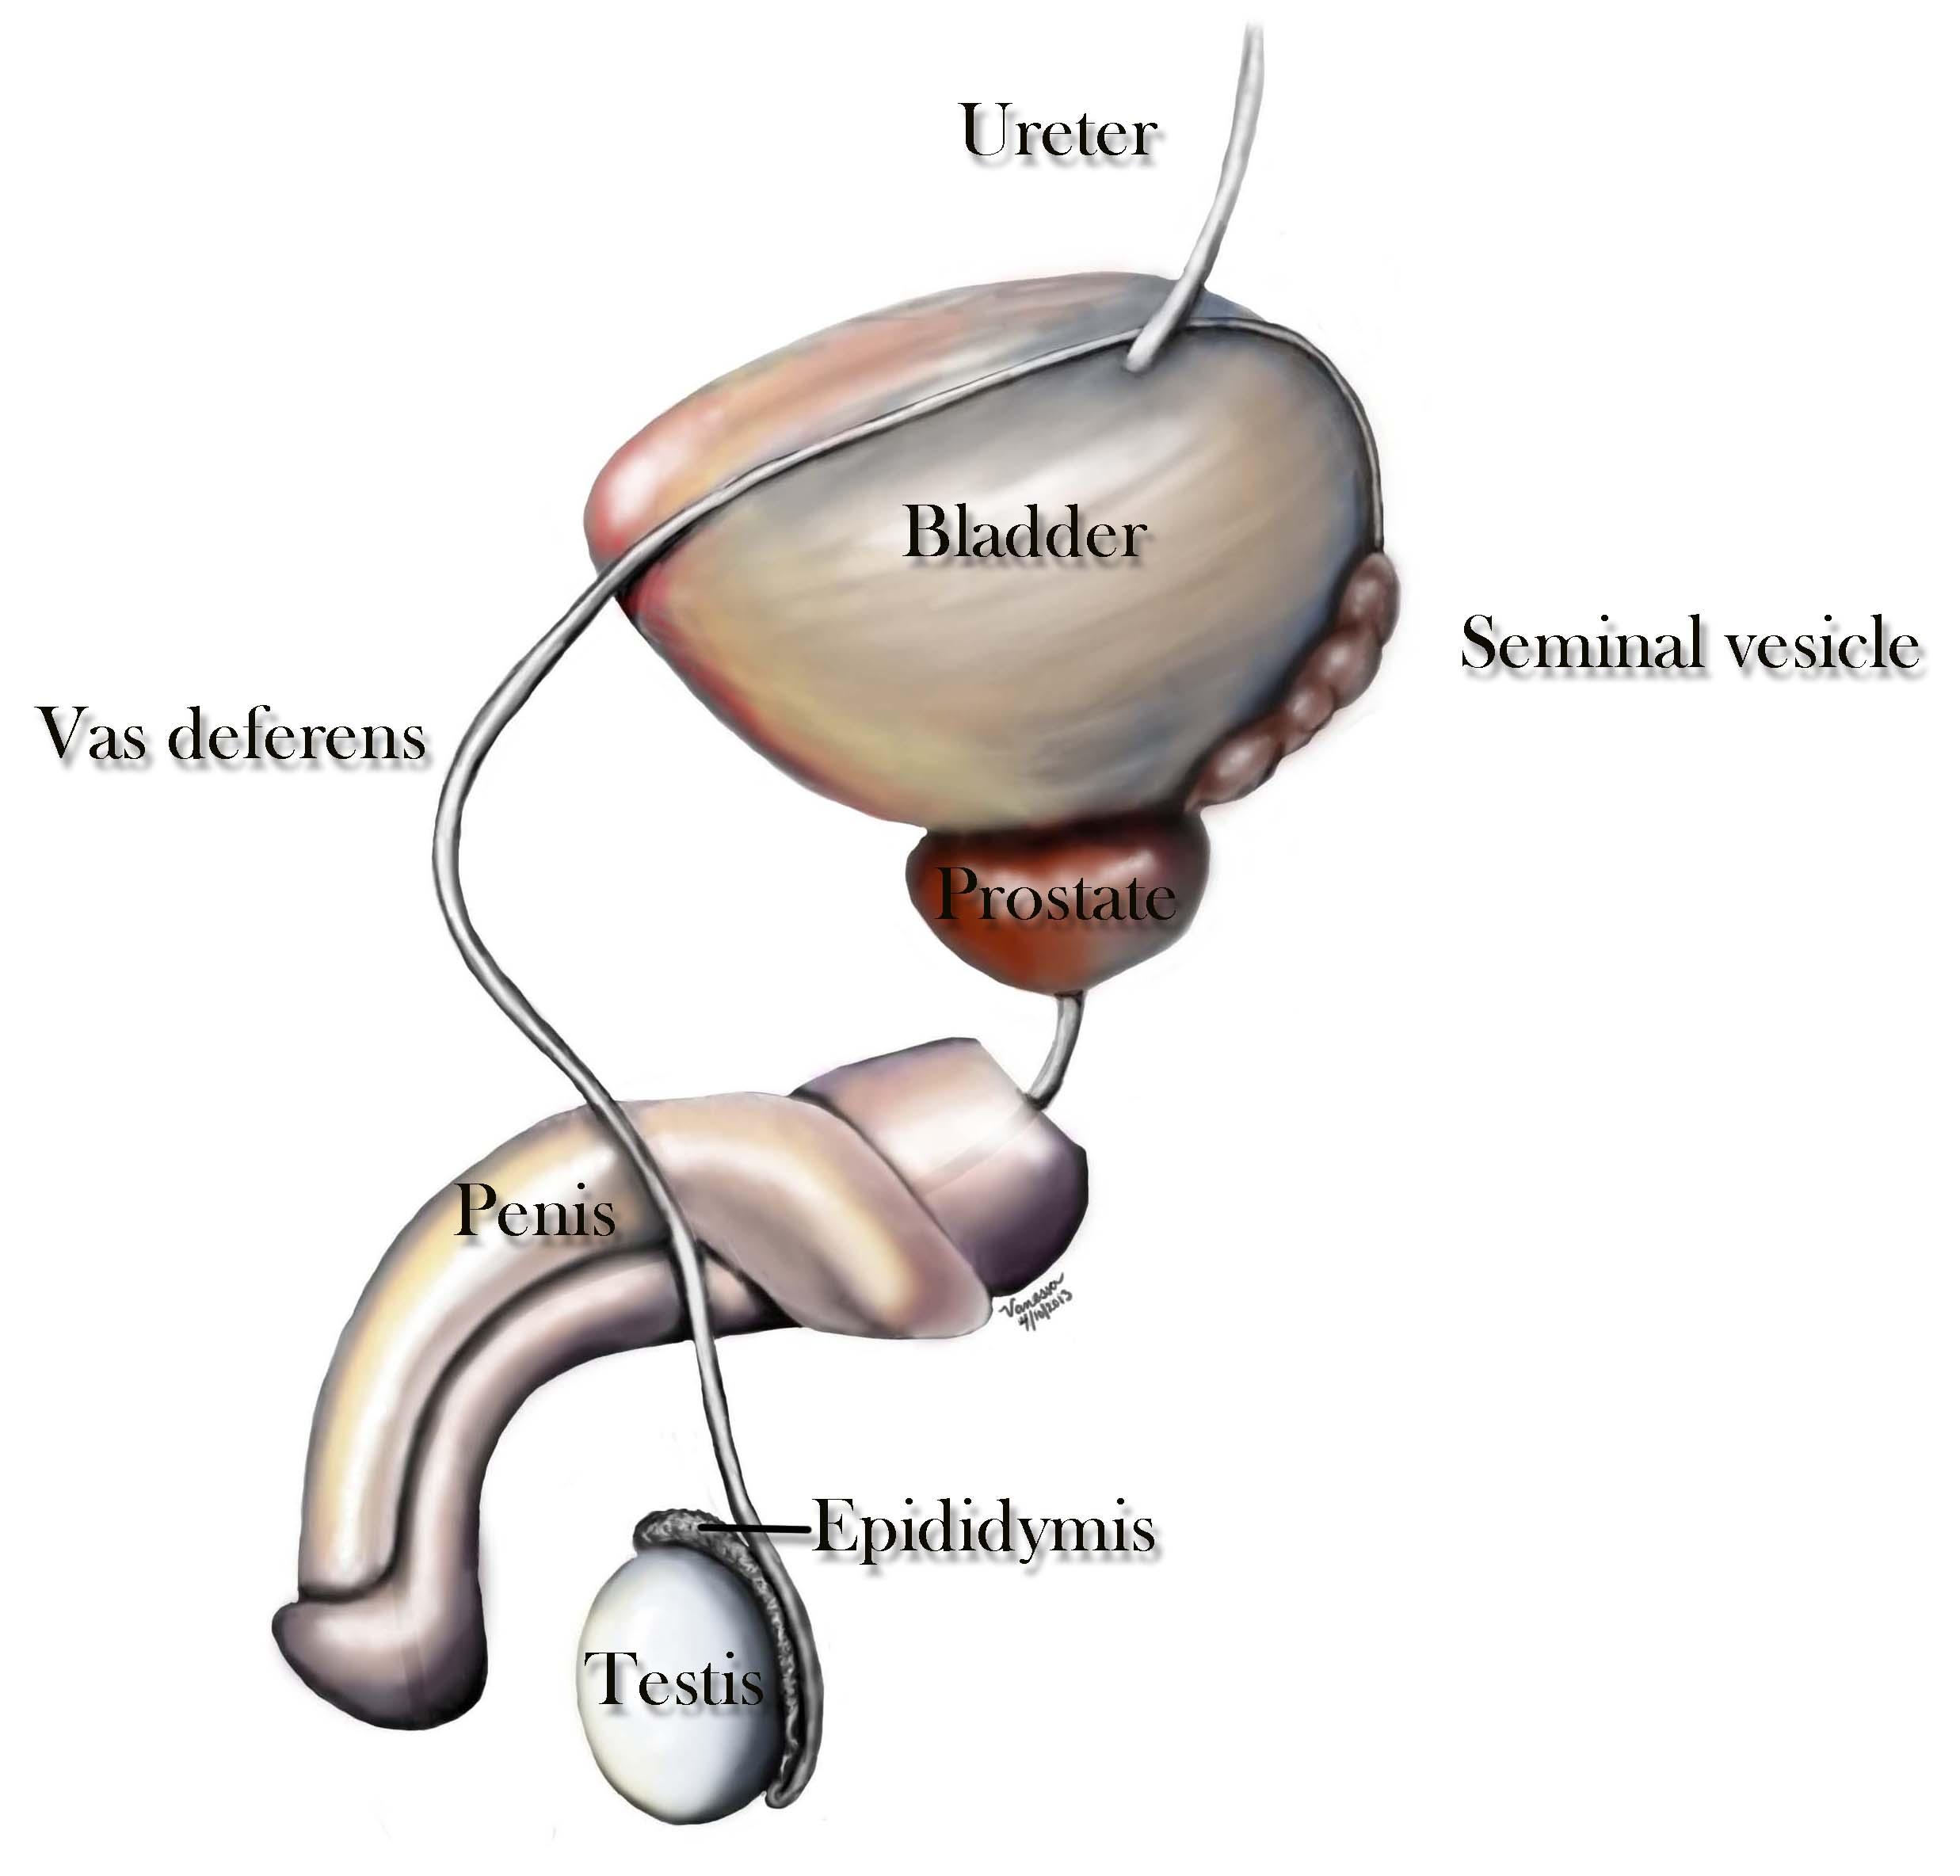

▼輸精管:位於男性睪丸旁邊的一條小管,專門負責將精子輸送到射精管,是男性生殖系統中非常重要的一個部分。